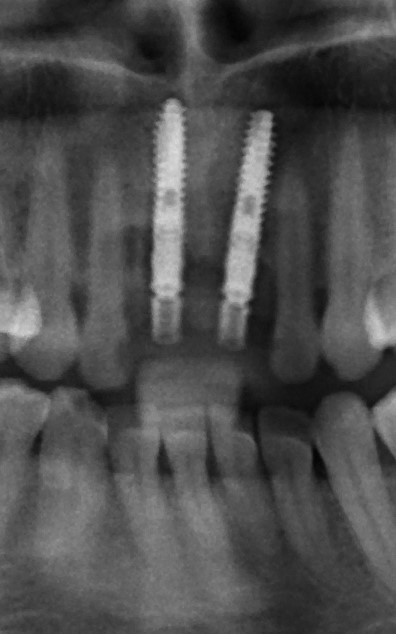

Рекомендации по установке имплантов. Для всех. Часть V.